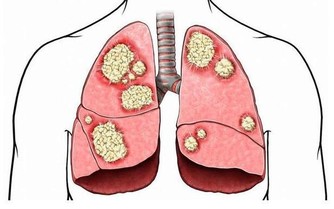

1、關節腫痛

日常生活中,很多人都會出現關節腫痛的問題,高尿酸就是其中的一個原因,如果體內的尿酸過高,就會有大量尿酸結晶,而這些結晶很難排出,只會留在我們的關節中。時間久了,就會出現關節疼痛的現象,這時建議及時去醫院檢查,查明原因,及時調理。